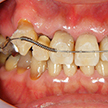

1. 初診時正面

この患者様の主訴は右下7番(第2大臼歯)の詰め物の脱離でした。口腔内写真を撮らせていただくと右上の八重歯(3番の唇側転移)が顕著でその叢生の結果、周囲が不潔となり歯肉炎およ2番(第2前歯)の歯頚部の異常他退縮が認められます。